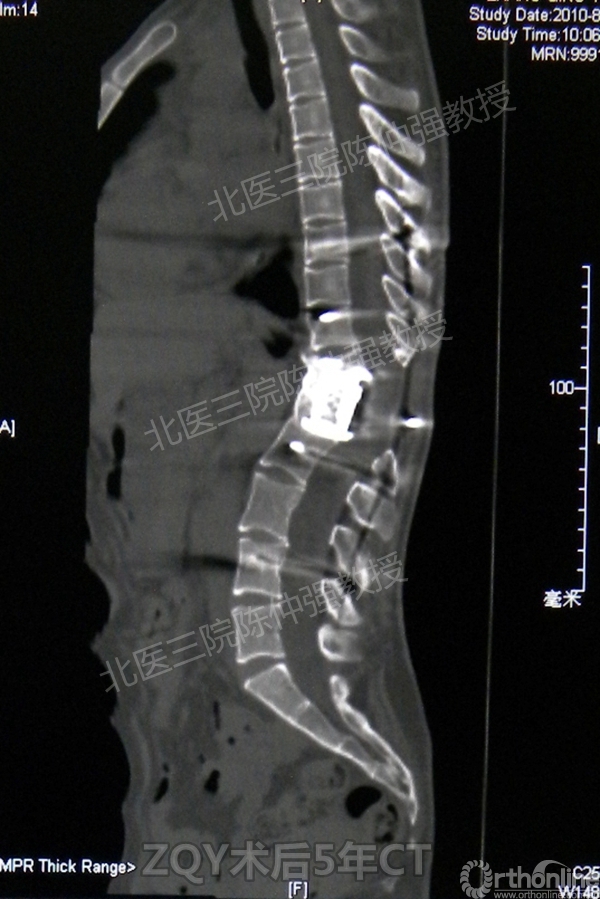

2005年,陈仲强教授在AOSpine年会上分享了一例胸腰椎陈旧结核性侧后凸畸形病例。资料如下:

ZQY术后5年

患者女性17岁,胸腰椎陈旧结核性侧后凸畸形,局部呈“麻花状”扭转,无神经功能受损表现。2005年,陈仲强教授带领团队实施后路+侧前方联合入路脊柱节段切除、双轴旋转矫形术。术后患者外观显著改善,神经功能正常。术后随访证实患者截骨矫形节段骨性融合良好,矫形效果持续良好。